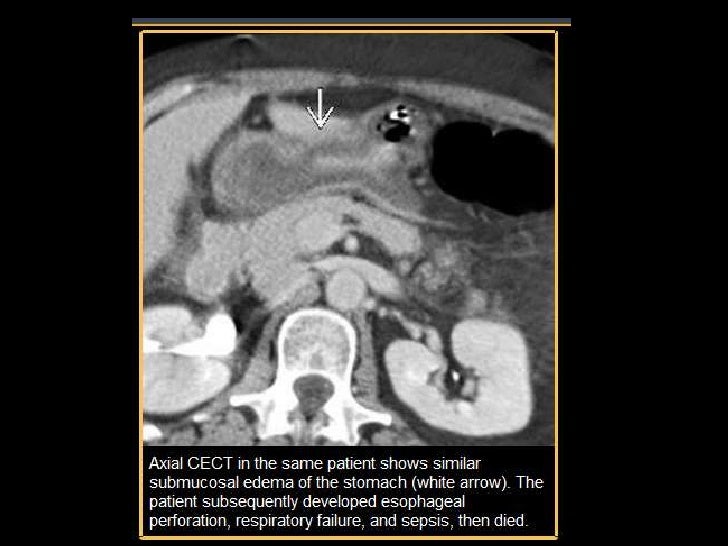

Figure 2Benign Strictures of the Esophagus and Gastric Outlet Caustic Esophagitis — esophageal motility studies report low amplitude and nonperistaltic. — caustic substances injure tissue by means of a chemical reaction on direct physical contact. — caustic ingestion can cause severe injury to the esophagus and the stomach. — caustic ingestions are seen most often in young children between one and three years of age and can. Caustic Esophagitis.